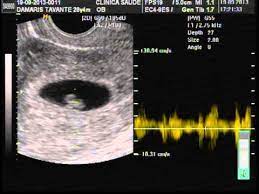

Ultrassom 6 Semanas E 3 Dias Do Nosso Bebe Youtube

Ultrassom 6 Semanas Video Dailymotion

Alice 1 Ultrassonografia 6 Semanas E 3 Dias Youtube